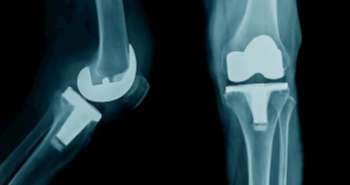

Diffuse and decreased osseous mineralisation and a comminuted distal femoral fracture were observed in X-ray findings of the right lower extremity. Similarly, significant diffuse osteopenia was also seen on X-ray of the left upper extremity. The distal phalanx of the index finger was found fractured as per the X-ray study of the right hand. Computed tomography (CT) scan of the pelvis and abdomen showed widespread brown tumors, florid changes of renal osteodystrophy and remarkable diffuse severe demineralisation of the bones, with prominent subligamentous resorption in the sacroiliac joints bilaterally.